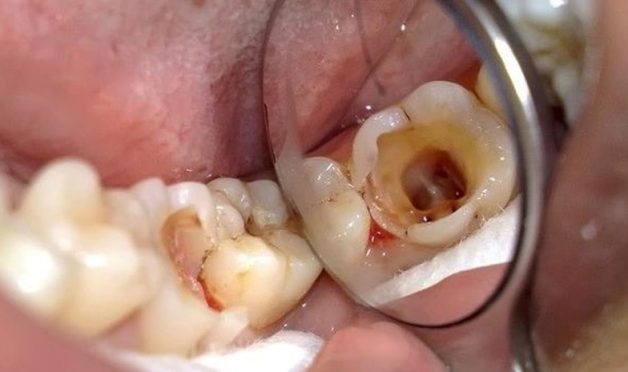

Răng sâu bị vỡ là nguy cơ khi đã sâu vào đến tủy

Sâu răng thường được chia thành 4 giai đoạn, tương ứng với 4 mức độ sâu của răng. Và tình trạng răng sâu bị vỡ thường xảy ra ở giai đoạn sâu răng nặng nhất:

– Giai đoạn 4: Chết tủy

Viêm tủy trở nên nặng hơn gây chết tủy. Đây cũng là giai đoạn xảy ra tình trạng răng sâu bị vỡ, mẻ khi cắn hoặc ăn nhai do răng đã trở nên yếu hơn hẳn. Không chỉ vậy, trong một số trường hợp răng bị nhiễm trùng nặng có thể sẽ phải chỉ định nhổ bỏ hoàn toàn răng hoặc sẽ gây biến chứng nguy hiểm do nhiễm trùng lan rộng, thậm chí có thể gây tử vong.